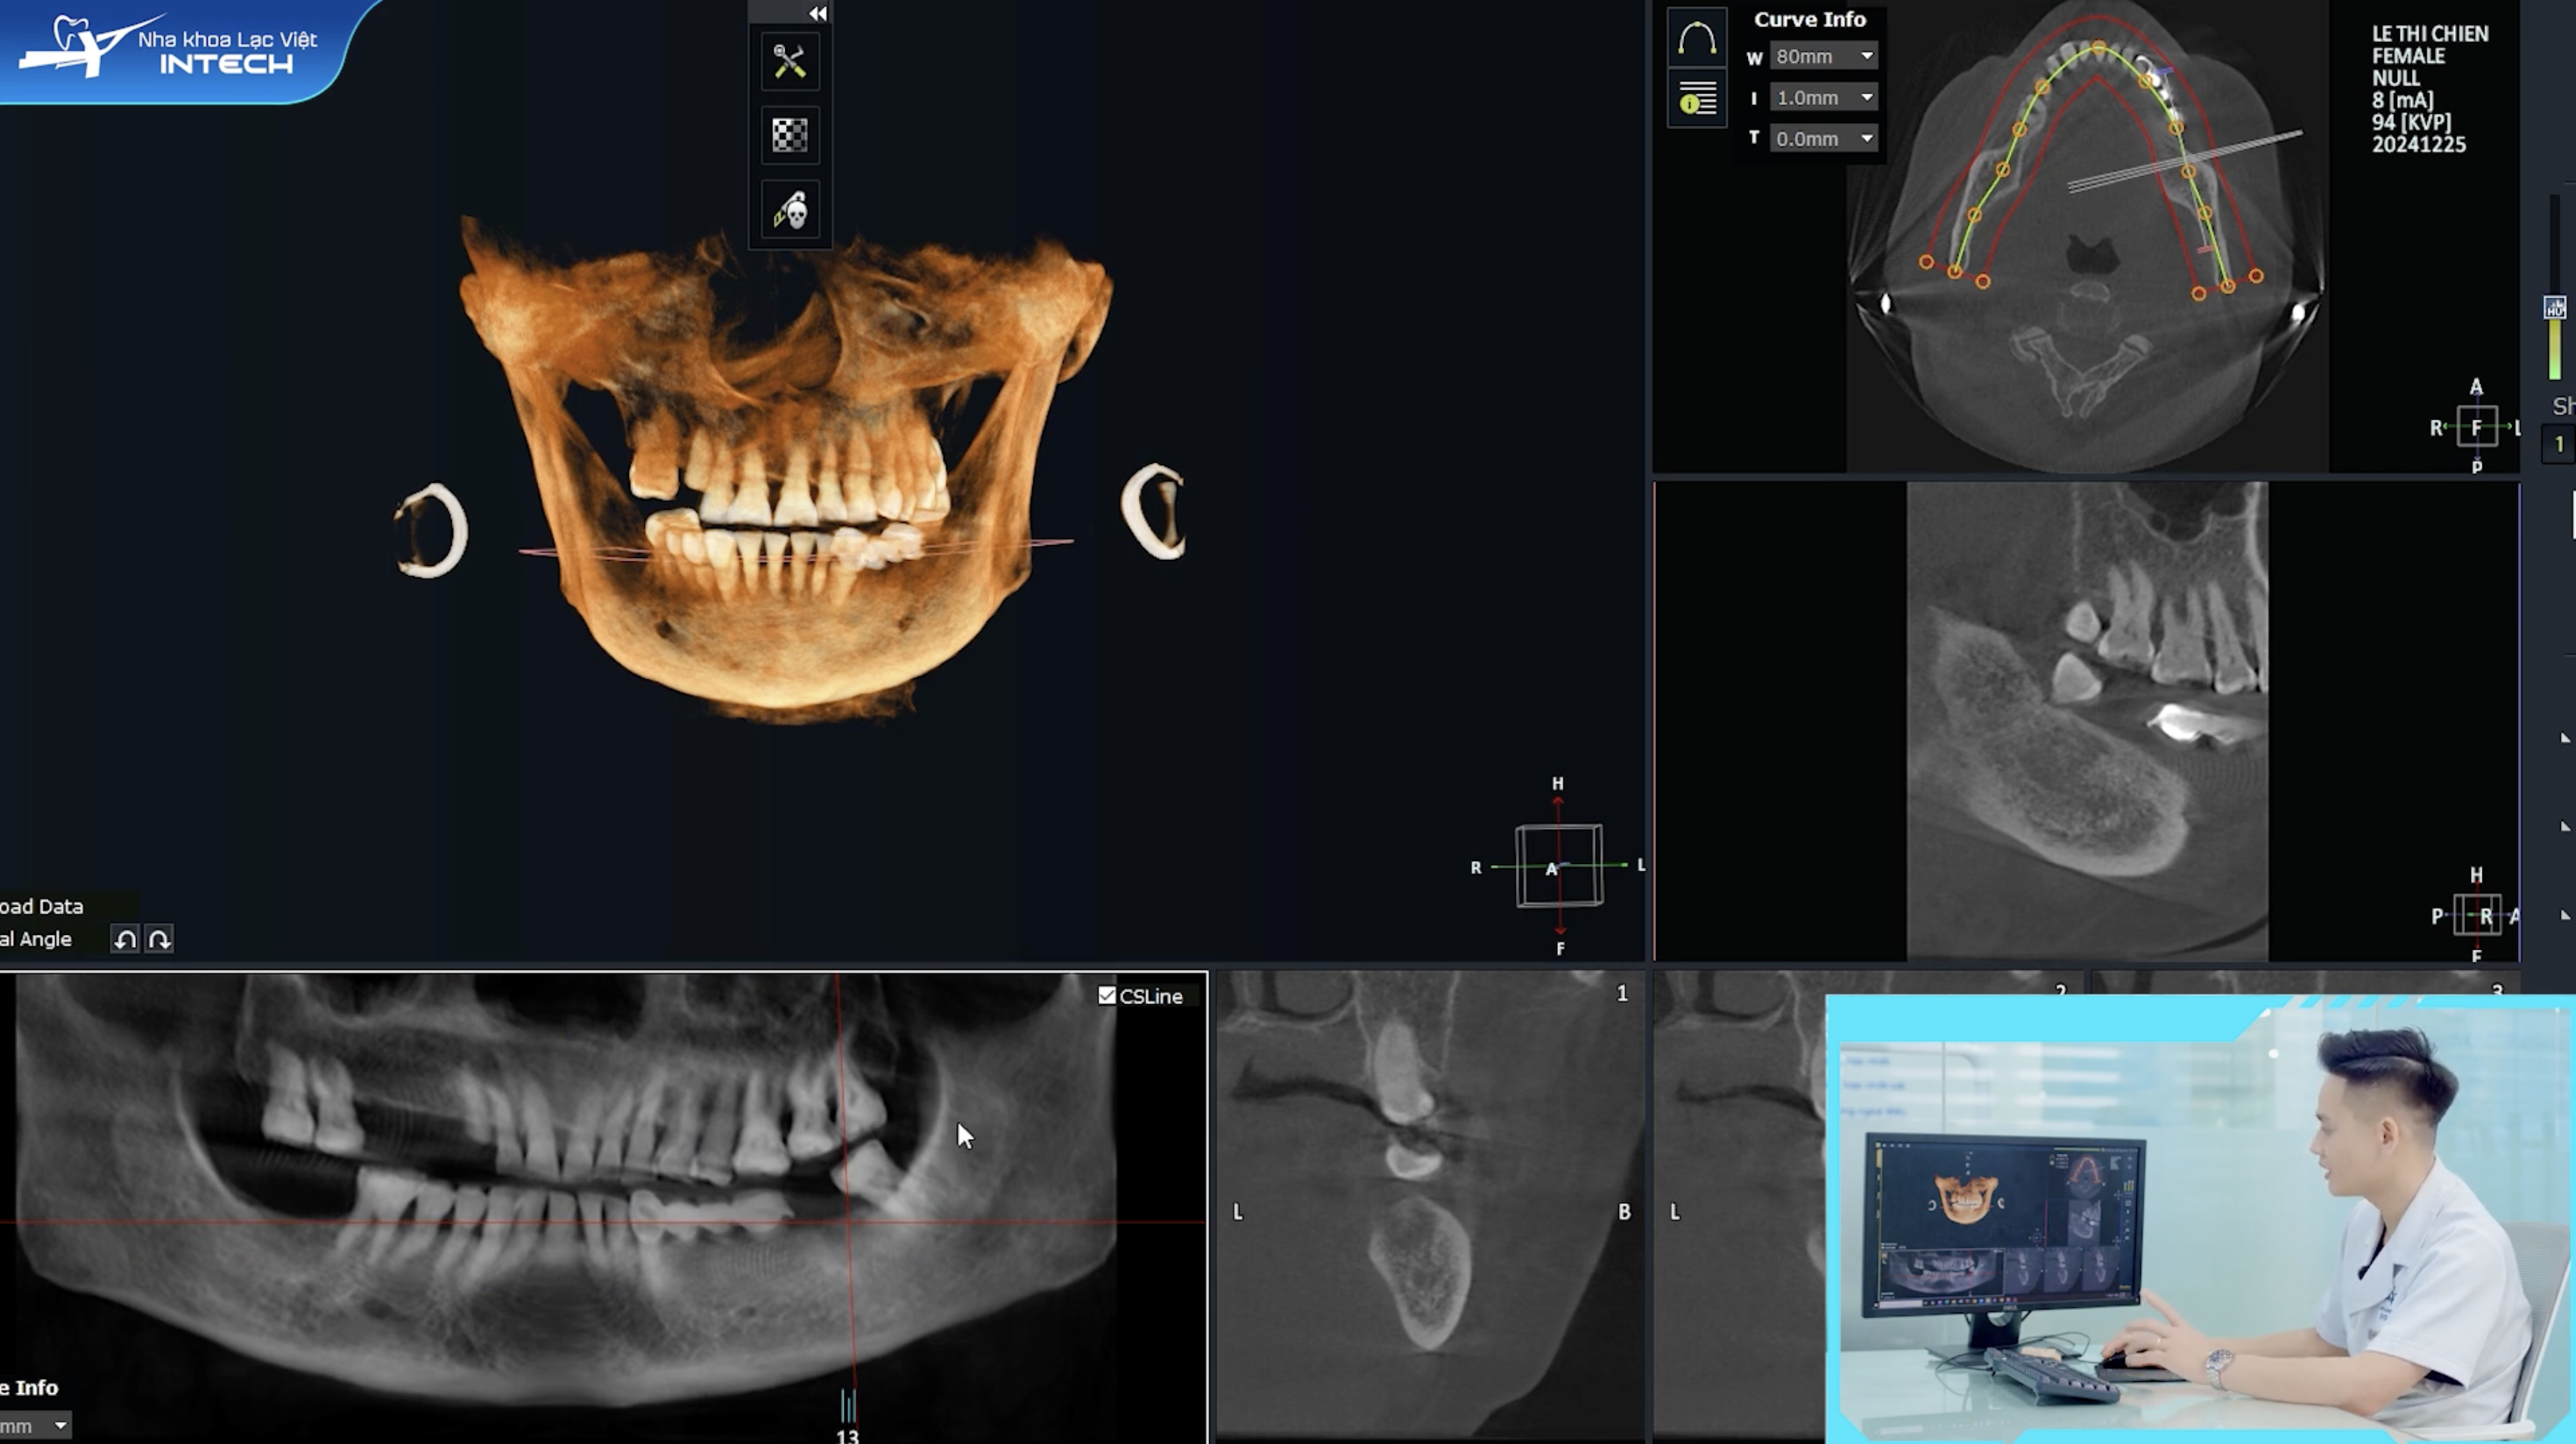

Việc xác định chính xác cấu trúc giải phẫu là vô cùng quan trọng để tránh đau khi cấy implant. Các cấu trúc như dây thần kinh, động mạch, tĩnh mạch và xoang hàm rất nhạy cảm. Nếu không xác định chính xác, việc cấy ghép có thể ảnh hưởng đến các cấu trúc này, gây ra những cơn đau sau Implant.

Tại Nha khoa Lạc Việt Intech, tất cả các trường hợp cấy ghép Implant đều được chụp phim CT Cone Beam 3D. Loại phim này giúp bác sĩ xác định chính xác cấu trúc giải phẫu quan trọng, đặc biệt là ống dây thần kinh hàm dưới. Từ đó, bác sĩ có thể tính toán khoảng cách xương và chọn kích thước trụ Implant phù hợp, đảm bảo an toàn tuyệt đối, loại bỏ nguy cơ biến chứng và giảm thiểu cơn đau.

Phim chụp CT Cone Beam 3D giúp các bác sĩ xác định chính xác các cấu trúc giải phẫu quan trọng